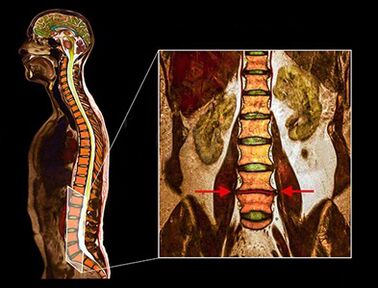

- The above diagnostic methods are usually sufficient to diagnose osteochondrosis, but accurate diagnosis requires the use of visualization methods.

- Ct

- Radiography

- Msct

- Pat

- MRI - This diagnostic method allows you to clarify the degree of degeneration, the presence of fractures, hernia on the stency discs.Often, a MRI study is needed to prepare for surgical treatment to determine the location of the degenerated disk and to plan the operation.

Studies have shown that the results of MRI with moderate or significant discs are found when scanning patients, both with severe pain and with minimal or lack of pain.In addition, many painful conditions may not occur on MRI.For this reason, the diagnosis cannot be made exclusively on the basis of the results of the visualization, and the examination of the diagnosis is possible only on the basis of the set of all clinical and instrumental examination methods.